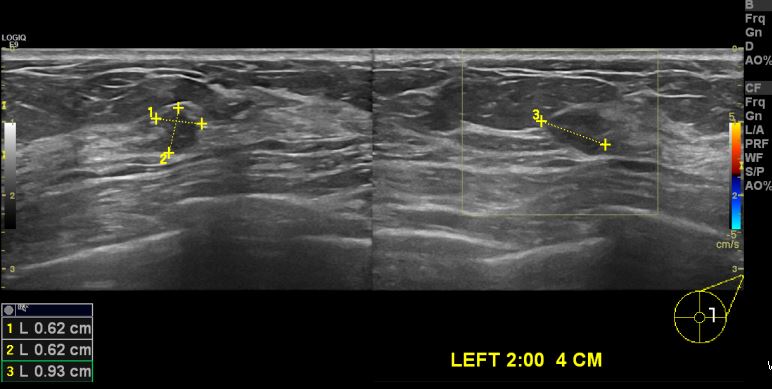

상기 환자 건강검진상 이상소견으로 내원하신 50대 여성분으로 좌측 2시 방향에 4cm 떨어진 거리에 의심스러운 혹 조직검사 시행하여 침윤성 유관암 진단되었습니다.